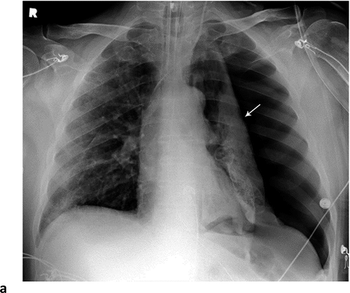

Research reveals lung findings not typically associated with viral pneumonia.